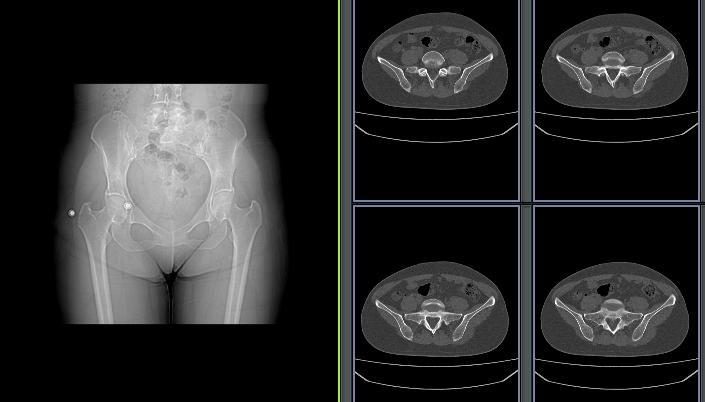

骨盆ct平扫图片解剖图

骨盆ct平扫图片解剖图,骨盆ct断层解剖图

诊断思路分析丨盆腔脏器病变(ct平扫 增强)

骨盆,股骨头平扫

正常女性盆腔CT影像图

正常骨盆ct平扫图片

骨盆CT解剖

盆腔CT解剖图